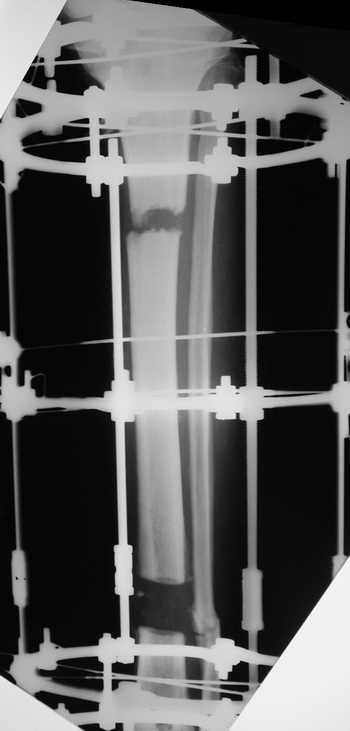

Мужчина, 33 года, резекция б\б кости по поводу остеомиелита после открытого перелома. Стандартная методика билокального остеосинтеза (рис 1 и 2). В конце удлинения выявилось неудовлетворительное взиморасположение перемещенного фрагмента и дистального отломка (рис 3). Планирование (рис 4).